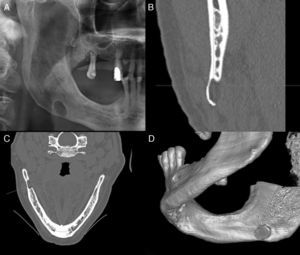

A 54-year-old Caucasian male, was referred by his dentist, on the finding, of a right mandibular radiolucent image, detected in a panoramic radiograph for a prosthetic rehabilitation study. During anamnesis the patient reported oro-facial diffuse pain, and did not mention any history of previous surgery or oro-facial trauma. No swellings were detected in intra-oral, facial and neck examination. The patient presented a brachyfacial type profile. Several teeth were absent. There was pain on palpation of the masticatory muscles. The panoramic radiograph revealed a well-demarcated, oval, unilocular radiolucent lesion, measuring 1.5cm in the mesio-distal diameter, located in the posterior region of the right side of the mandible unrelated to teeth and beneath the mandibular canal (Fig. 2A). The orofacial pain was related with the absence of posterior inferior teeth and the mandibular lesion was a probable PL-MBD. A CT-scan with three-dimensional reconstruction was performed (multislice CT Thoshiba® Aquilion S16, Zoetermeer, Netherlands, 1mm-thick slices) and revealed an osteolytic image of 1.5cm in mesio-distal diameter, with a lingual opening limited by a bony cortical lining containing an image compatible with soft tissues (Fig. 2B–D). The final diagnosis of this concavity was PL-MBD. No treatment of PL-MBD was performed, keeping the patient under clinical and radiological surveillance. After 2 years of follow-up the defect remained without alterations.

(A) Panoramic radiograph reveals a well-demarcated, unilocular radiolucent area in the lower left angle of the mandible. (B) Axial cone-beam CT showing a lingual opening of the PL-MBD, containing soft tissue inside compatible with glandular tissue. (C) CT with three-dimensional reconstruction image.